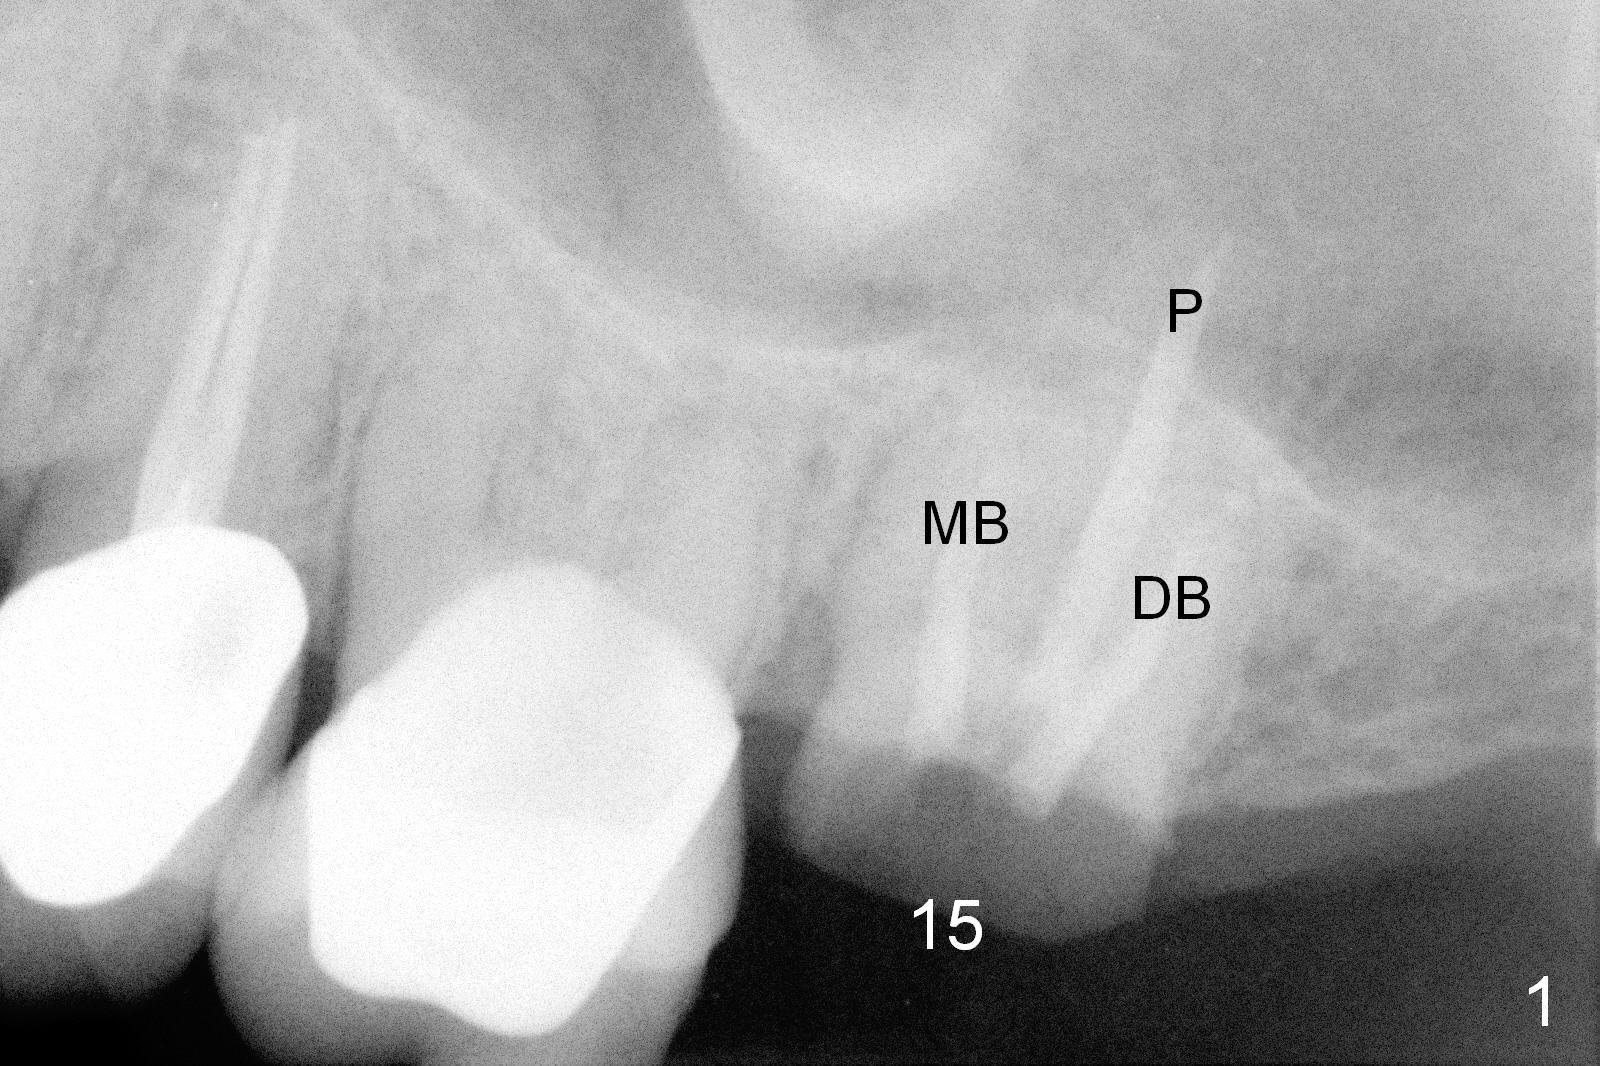

The tooth #15 of a 62-year-old man (CY) has been fractured for 4 years (Fig.1). The 3 roots (MB, DB and P) appear to be approximated each other (Fig.1,3,4) so that when the tooth is extracted (using a surgical handpiece for sectioning), the socket should be single and large. Treat the socket with Clindamycin. If the socket proves to be flat on the top, the thickness of the sinus floor is approximately 2 mm. If the bone is not so tough, use osteotomes to do sinus lift; otherwise use drills. The depth of osteotomy should be tightly monitored.

PA shows that the depth of the osteotomy is approximately 17 mm (Fig.2), whereas CT 14 mm (Fig.3,4). Intraop measurement will determine the depth.